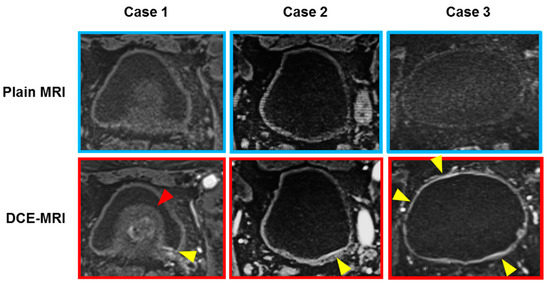

2.4. DCE-MRI Scan Protocol

2.5. Image Interpretation for Bladder Lesions